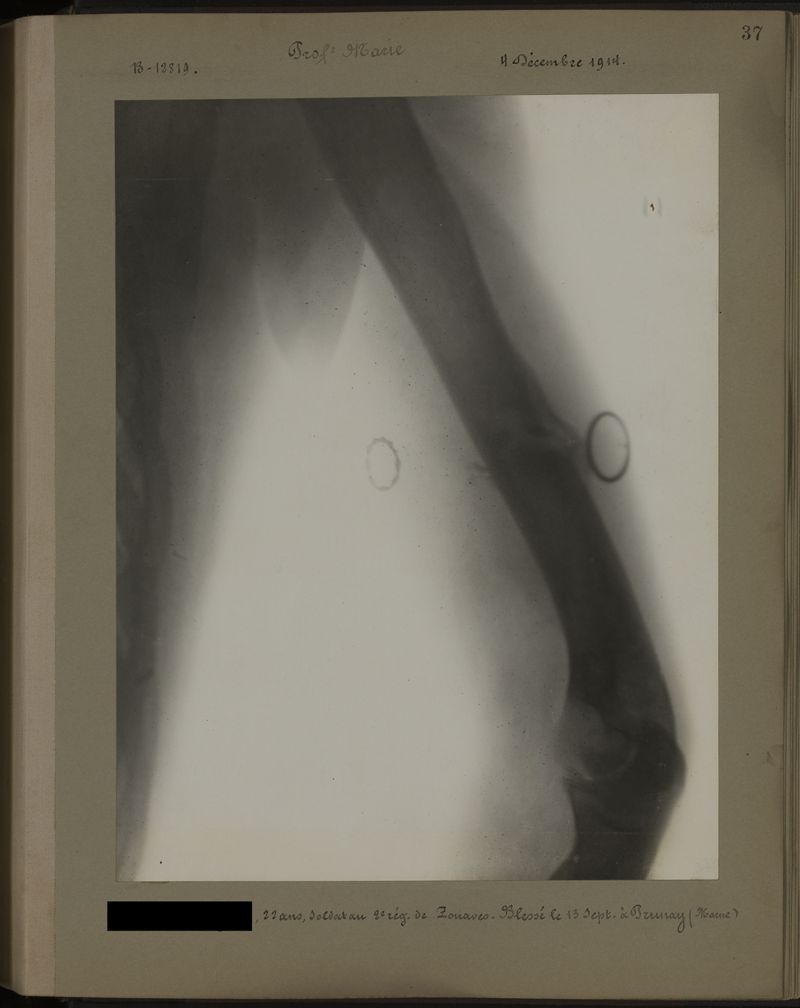

Deux albums de radiographies de la Première Guerre mondiale. Collection du laboratoire central de radiographie de la Salpêtrière. Deuxième album.

1915.